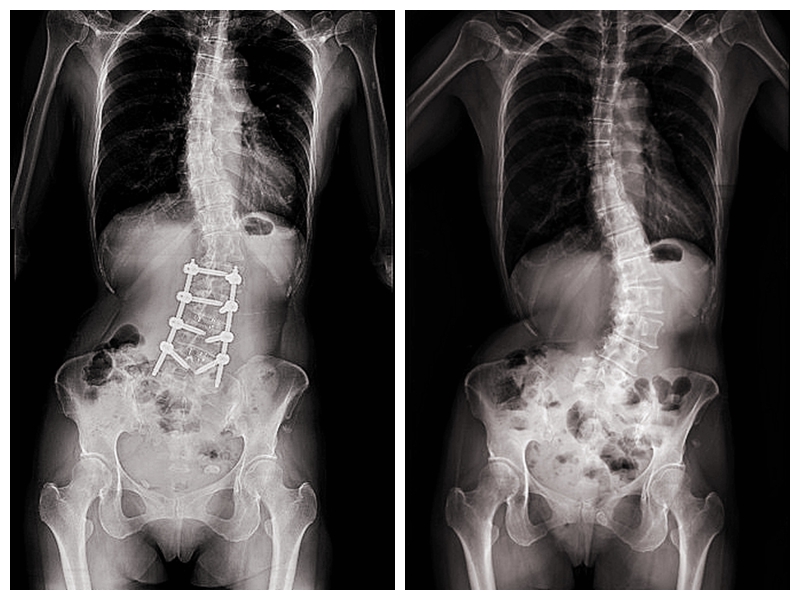

經友人推薦至臺中市立老人復健綜合醫院(下簡稱 中醫大市醫)骨科就醫,由微創脊椎中心助理副院長張建鈞醫師評估後,決定接受3D導航微創矯正手術。術後從47度矯正至10度,身高增加約5公分,25年的宿疾大幅改善,終於能安穩入睡。 張建鈞醫師指出,患者因長期未治療,脊椎側彎角度已達48度,屬中重度退化性脊椎側彎,加上合併二尖瓣膜脫垂心臟病史,進行傳統開放式手術風險極高。

經完整影像評估與跨科討論後,醫療團隊建議採取「微創前開3D導航矯正手術」,在不大幅破壞背部肌群的情況下,從側邊小切口進行矯正與支撐重建。手術後恢復快速,術後4至5天即順利出院,疼痛明顯減輕。黃小姐笑說,術後穿著背架反而帶來前所未有的安全感,甚至捨不得太快卸除。 共同執行手術的骨科部副部長林琮凱醫師進一步說明,脊椎側彎(Scoliosis)是指脊椎向側面異常彎曲,並伴隨椎體旋轉變形,並非單純姿勢不良。